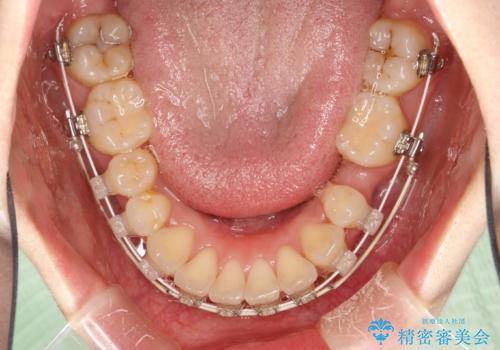

抜歯をして前歯を下げ、ガタつきを取り除く ワイヤー矯正

- 上顎両側第1小臼歯、下顎左側第2小臼歯の3本を抜歯、ラビアルのワイヤー矯正を計画した。